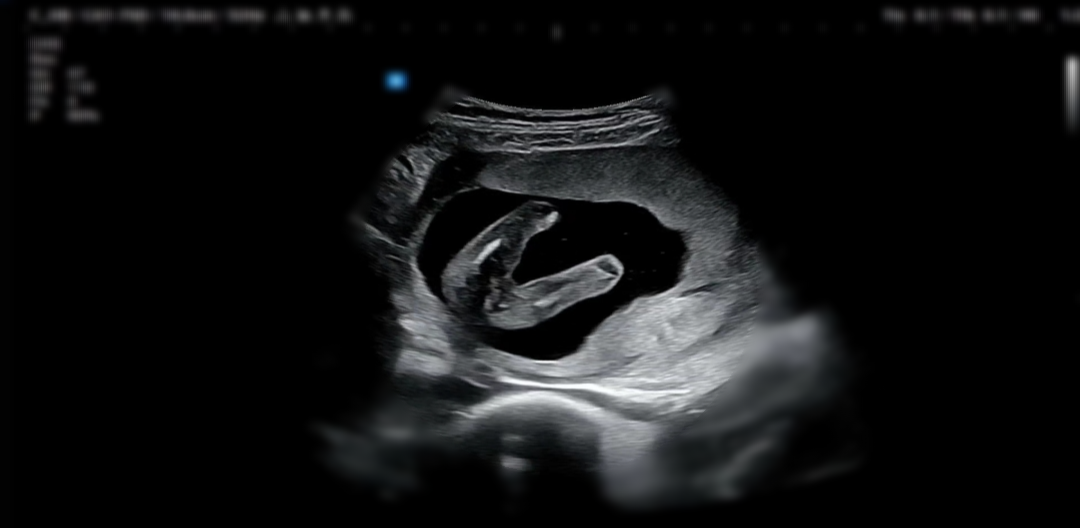

평일에 반차를 쓰고 정기점검 날이라

병원에 갔다!

새리는 여전히 잘 자라고 있었고ㅎㅎ

신경관 결손 검사를 위한 피검사를 진행하였다

초음파를 보자마자 귀로 손을 막고있는 새리 발견

시끄러운 건가 싶었는데

찾아보니 아마 우연의 일치일 거라고 한다

남편이 지나치게 귀가 밝아서ㅠ

그것만은 닮지 않기를!!!

우리 새리의 성별은

👸공주님!!!!!!!

다리사이가 아주 깨끗했다!ㅋㅋㅋ

딸이라니!!!!!!!!!!!!!

너무 기대된다!!!!